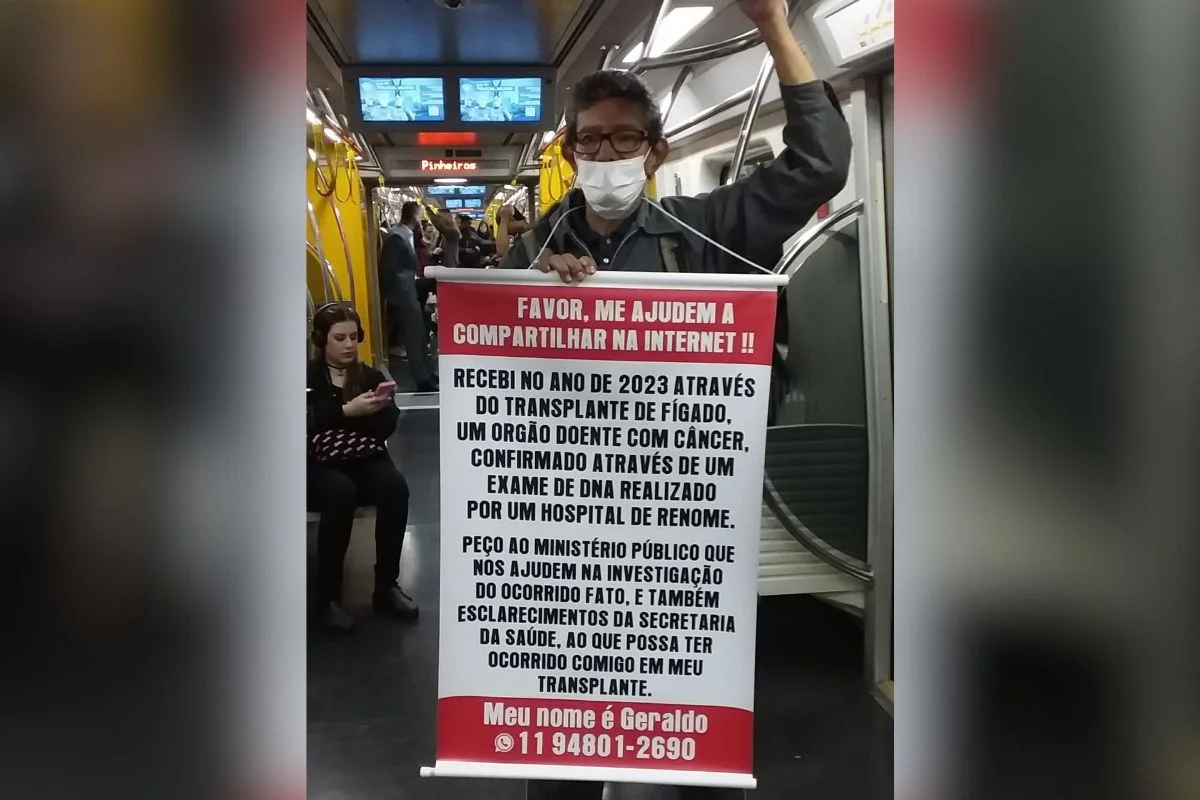

Agora, tanto ele quanto a esposa, Márcia Helena Vaz, decidiram falar. Ela, que está em campanha com o marido nas redes sociais e pelas ruas de São Paulo desde setembro deste ano, confessou ao Metrópoles que eles lutam por explicação e investigações sobre o que pode ter ocorrido no procedimento, tão comum no país.

“Não cabe, nesse caso, um silêncio institucional. Por favor, não cabe. Não cabe porque isso dá margem para que o erro continue acontecendo. O silêncio produz isso. Uma margem para que o erro continue acontecendo”, desabafou Márcia.

Paciente e esposa estão movimentando as redes sociais e indo às ruas divulgar sobre o caso